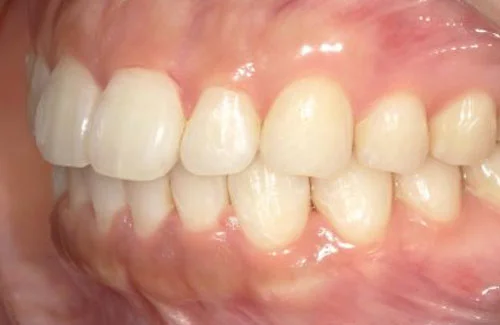

<症例2>歯が全体的にガタガタ、出っ歯でお悩み

歯列のアーチがやや狭く、それにより上下の前歯部にガタつきが生じている状態でした。

小臼歯部をわずかに広げてスペースを作ることで、お口元を整えつつガタつきを改善しています。

患者様と症状

主訴:全体的なガタガタ、出っ歯

性別・年齢:30代女性

問題点:上下前歯部の叢生(中程度)、ディープバイト

診断:前歯部の叢生を伴うアングルⅠ級の不正咬合

主なリスク:矯正中一時的に咬合しにくくなる、歯肉退縮

症状:叢生(そうせい) 過蓋咬合(かがいこうごう)

治療内容

治療期間:9ヶ月

治療費用:660,000円(税込)

プラン:26枚コース/モデレートプラン

抜歯:親知らずのみ抜歯

再診治療費:無し

追加治療費:無し

保定装置費:無し

治療前後の写真